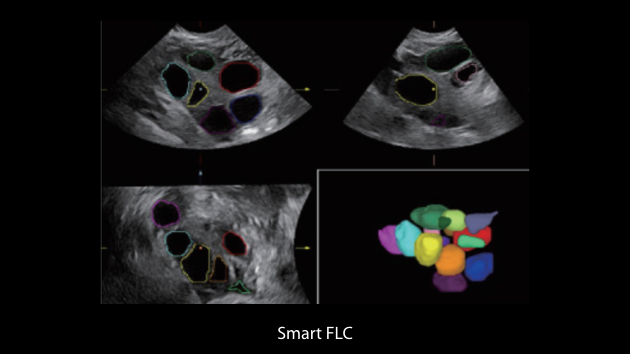

Nuewa I9, kad?nlara ve yenido?anlara y?nelik sa?l?k hizmetleri i?in ?zel olarak tasarlam??t?r ve i?ten d??a yenilik?i bir deneyim sunmaktad?r. Bu yenilikler, karma??k klinik senaryolara ili?kin derinlemesine bilgilere dayal? olarak geli?tirilmi?tir ayr?ca do?ru ve zaman?nda yan?tlar?n yan? s?ra, ola?an├╝st├╝ verimlilik ve ola?an├╝st├╝ kullan?c? deneyimi sunar.